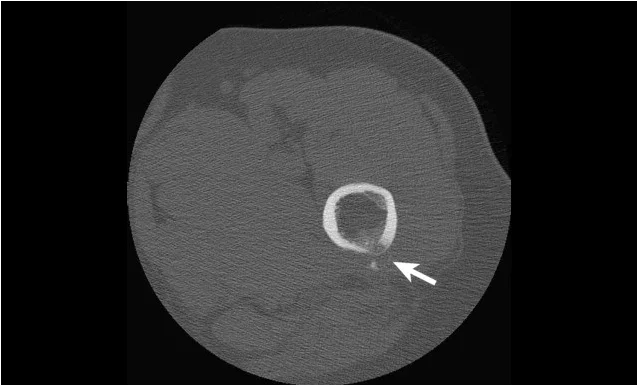

Изображение: Hellerhoff, CC BY-SA 4.0, via Wikimedia Commons

Рамото е най-често засегнатата става от калцифициращ тендинит. Сухожилието на мускул супраспинатус се засяга най-често, следвано от сухожилията на инфраспинатус, терес майор и субскапуларис. Калциевите отлагания се търсят на местата на закрепване на сухожилията на ротаторния маншон върху главата на раменната кост. Двустранно засягане се наблюдава при 20%–30% от пациентите.